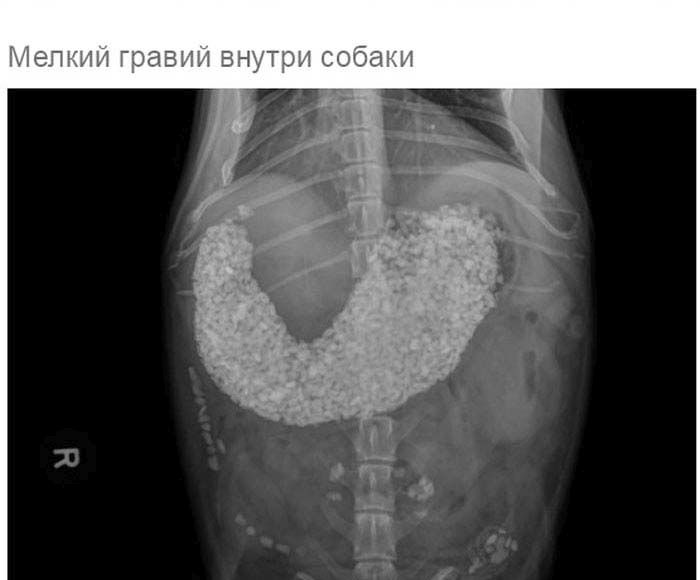

» Что может оказаться в желудке собаки

Что может оказаться в желудке собаки